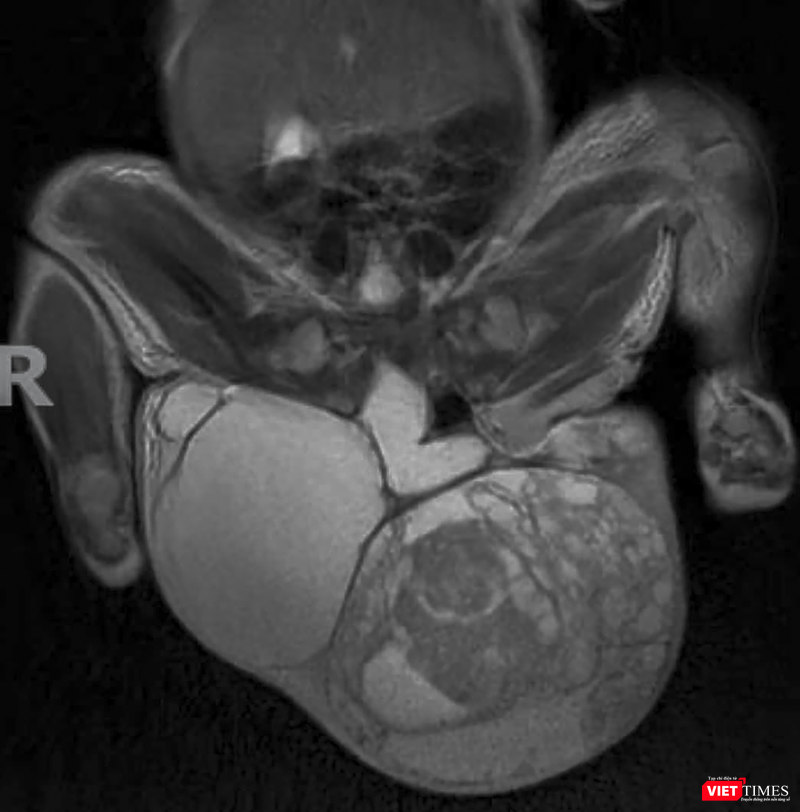

ThS.BSCK2. Nguyễn Phi Phong – Khoa Ngoại nhi, Bệnh viện Phụ sản – Nhi Đà Nẵng - cho biết, trẻ là con của sản phụ ở Kon Tum. Khối u được phát hiện lúc thai 18 tuổi và theo dõi thai tại Bệnh viện Phụ sản – Nhi Đà Nẵng. Khi đủ tháng, trẻ được sinh mổ, chào đời với cân nặng 3,2kg. Tuy nhiên sau sinh, ở vùng cụt của trẻ có khối u lớn hơn 15cm và nặng hơn 1,2kg.

Sau khi chẩn đoán và hội chẩn thống nhất phương án, các bác sĩ Khoa Ngoại nhi đã phối hợp với Khoa Nhi sơ sinh và Khoa Gây mê tiến hành phẫu thuật cắt khối u. Ca phẫu thuật kéo dài hơn 2 tiếng, khối u đã được cắt bỏ thành công. Kết quả giải phẫu khối u cho thấy là hỗn hợp dịch, xương, lông tóc và mô mềm.

“Khối u có nguồn gốc từ tế bào phôi thai. Mức độ ác tính tùy thuộc vào độ trưởng thành của khối u và độ tuổi mổ. Tỷ lệ gặp rất hy hữu từ 1/35.000 - 1/40.000 ca mắc. Hiện trẻ đang được tiếp tục hồi sức và điều trị sau mổ và chờ kết quả sinh thiết khối u để đánh giá và tiên lượng cuộc sống của trẻ sau mổ”- ThS.BSCK2. Nguyễn Phi Phong cho hay.